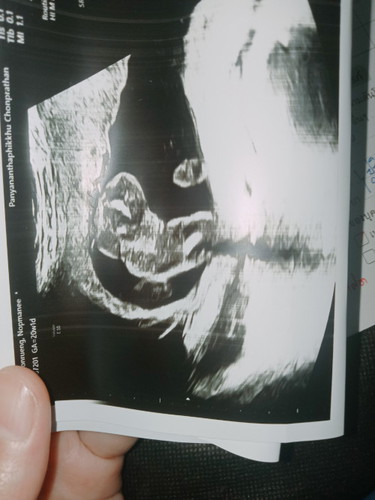

หมอแจ้งว่าน่าจะเพศหญิง แต่มีแต่คนทักว่าแม่จะได้ลูกชาย แบบนี้น้องจะเป็นหญิงไหม